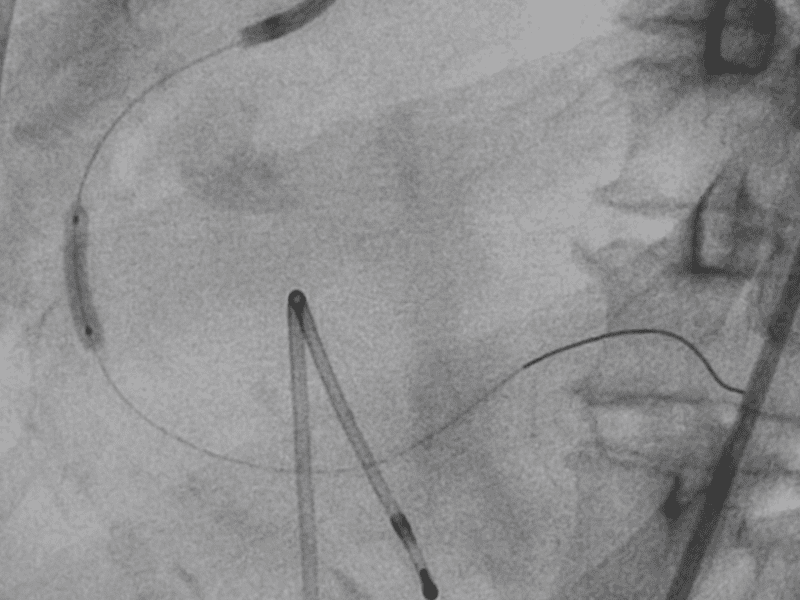

- Angioplastica: Un intervento minimamente invasivo per dilatare le arterie ristrette, ripristinando il flusso sanguigno.

- Bypass arterioso: Nei casi più gravi, un intervento chirurgico per creare una nuova via per il flusso sanguigno, bypassando le arterie ostruite.